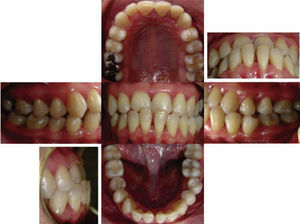

RESULTSThe arches were successfully correlated by eliminating the crossbite, the crowding was solved and the spaces were closed thus improving occlusal relationships and achieving molar and canine class I. The resulting overbite and overjet were adequate and remained under control. Periodontal status, aesthetics and function were favored (Figure 10) so the oral health and facial status of the patient was improved (Figure 11), emphasizing the harmony of a beautiful smile (Figure 12).

In the final cephalometry and in the superimposition, the skeletal changes were: initial facial depth: 94°, final: 92°; initial maxillary depth: 94°, final 95.4°; initial convexity: 0mm, final: 3.2mm; initial facial axis: 89°, final: 92.6°; initial Gn-GN/L1: 88°, final: 89°; initial SN/ U1: 100°, final 115° (Figure 13). It may be observed that a conservative treatment was performed since no surgical procedure was needed to correct the skeletal problem in addition to controlling periodontal health and improving the patient's esthetic conditions. However in order to achieve these results, the upper incisors were proclined (Figure 14).

It is important to emphasize that the use of fixed retainers in patients with a history of periodontal disease may be favorable because these type of retainers decrease secondary teeth movements and thus allows a positive environment for bone repair mechanisms. Interdisciplinary control remains important. In addition to the above-mentioned factors, a good retention can help achieve better results and a functional change for periodontally compromised patients with Class III malocclusion.2,13